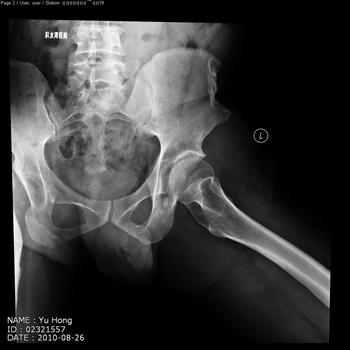

total hip replacement on hips with unilateral severe dysplasia and high riding